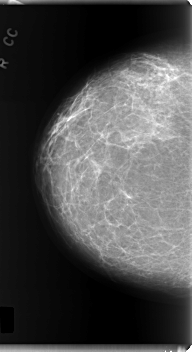

C_0220_1.RIGHT_CC

RIGHT_CC LINES 5968 PIXELS_PER_LINE 3248 BITS_PER_PIXEL 12 RESOLUTION 50 NON_OVERLAY